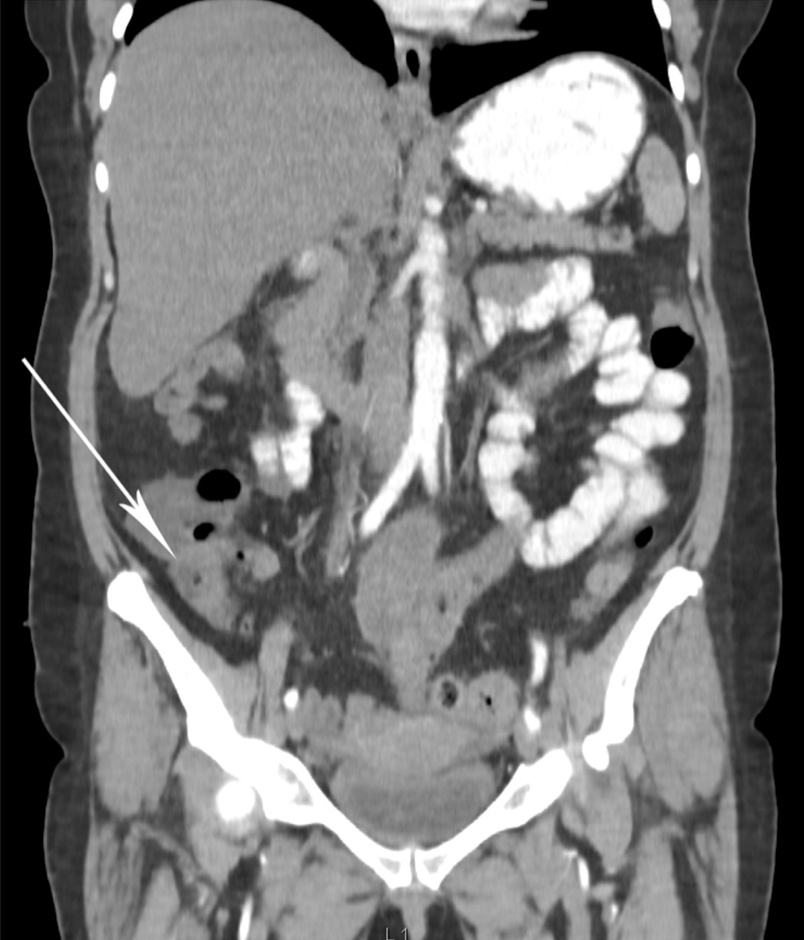

腹部CT

显示阑尾增大伴阑尾周围脂肪条索样改变,提示急性阑尾炎(图1)。

图1. 腹部CT